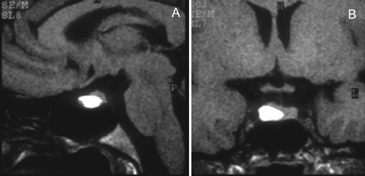

Las imágenes más características en la RM son un aumento de tamaño simétrico de la glándula pituitaria, una estructura homogénea pre y postgadolinio, con refuerzo intenso después de la inyección de contraste paramagnético. (Figuras 24A y 24B).

Figura 24 A y B. Hipofisitis, cortes sagitales, secuencias T1w antes y después de la inyección de Gadolinio, se observa aumento de volumen de la pituitaria y del infundíbulo, que muestran un refuerzo intenso y homogéneo (punta de flecha). Quiste de la bolsa de Rathke